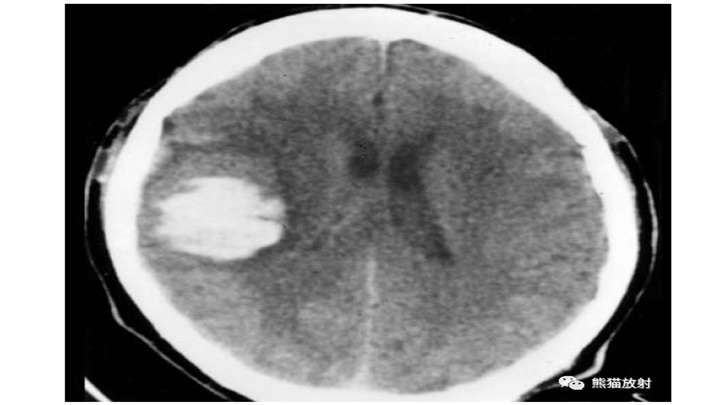

大量脑出血,累及左丘脑和基底节。明显的占位效应(中线结构向对侧明显移位)和脑室积血(同侧脑室变扁,右侧枕角积血)。然而,像往常一样,腹周水肿的数量仅限于周围边界。患者在数小时后死亡。